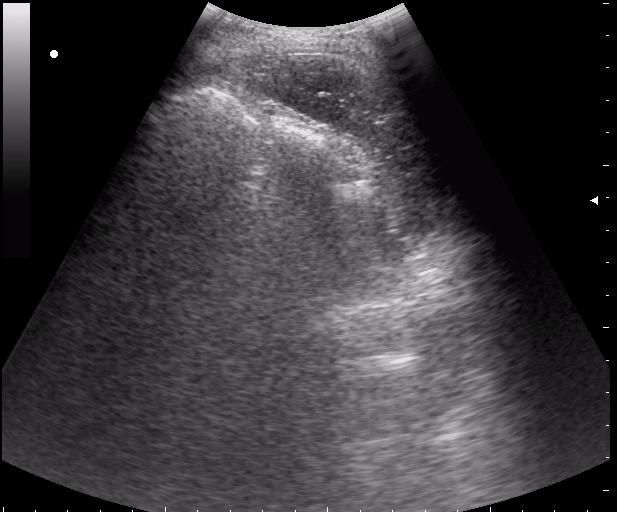

сегодня был селезёночный день.